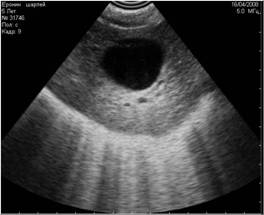

![]() |

Рис. 8. На снимке представлен гиперэхогенный объект в полости мочевого пузыря, испускающий эхоакустическую тень. На основании этого артефакта, мы можем предположить, что этот объект является конкрементом. |

Рис. 9. На снимке представлен похожий по величине и эхогенности объект в полости мочевого пузыря, не испускающий эхоакустической тени. На основании этого признака, мы можем предположить, что изучаемый объект является новообразованием. |